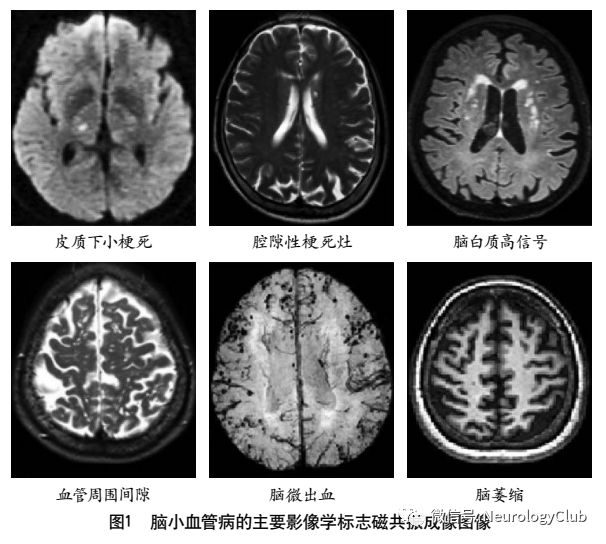

CSVD转化研究的影像学技术

2011年,美国医学研究委员会、德国神经退行性疾病研究中心和加拿大卫生研究院共同建立了神经退行性疾病精英中心。2013年,该中心的核心专家组成员共同撰写了CSVD的共识指南,确立了代表CSVD的6种关键性损伤的神经影像学标志(图1),分别是近期皮质下小梗死、假定血管源性的腔梗灶、假定血管源性的白质高信号、PVS、脑微出血和脑萎缩。现将CSVD影像表现的相关影像技术介绍如下。